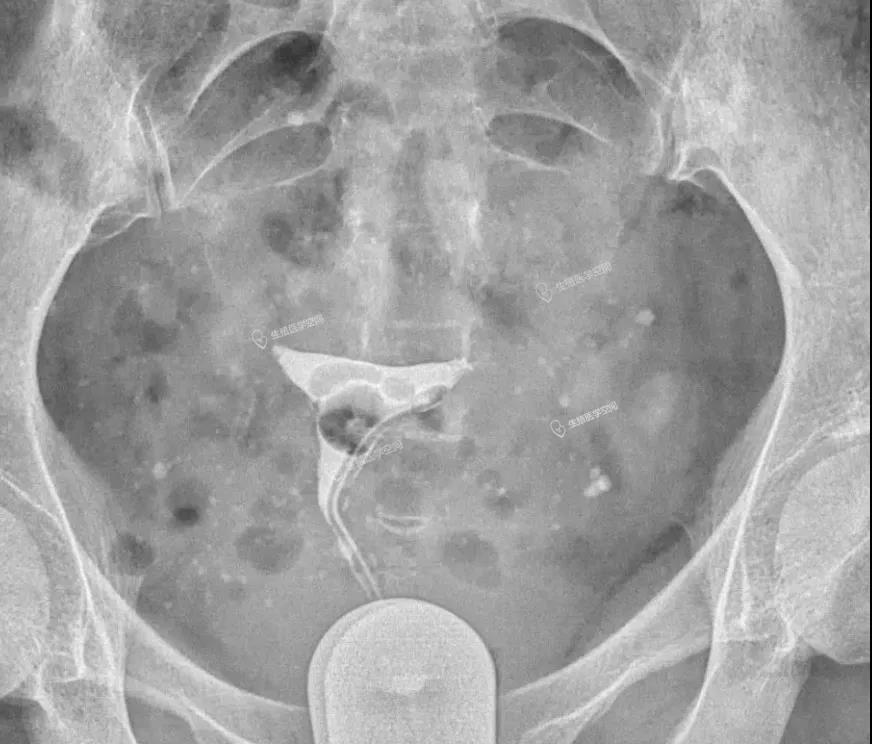

病例1 女 28岁 原发不孕,子宫输卵管造影发现双侧输卵管间质部阻塞,为结核性输卵管闭塞,不管是宫腹腔镜或放射科的介入再通术都疏通不成功。男方检查均正常。于是做试管婴儿。37周多剖宫产一对双胞胎。